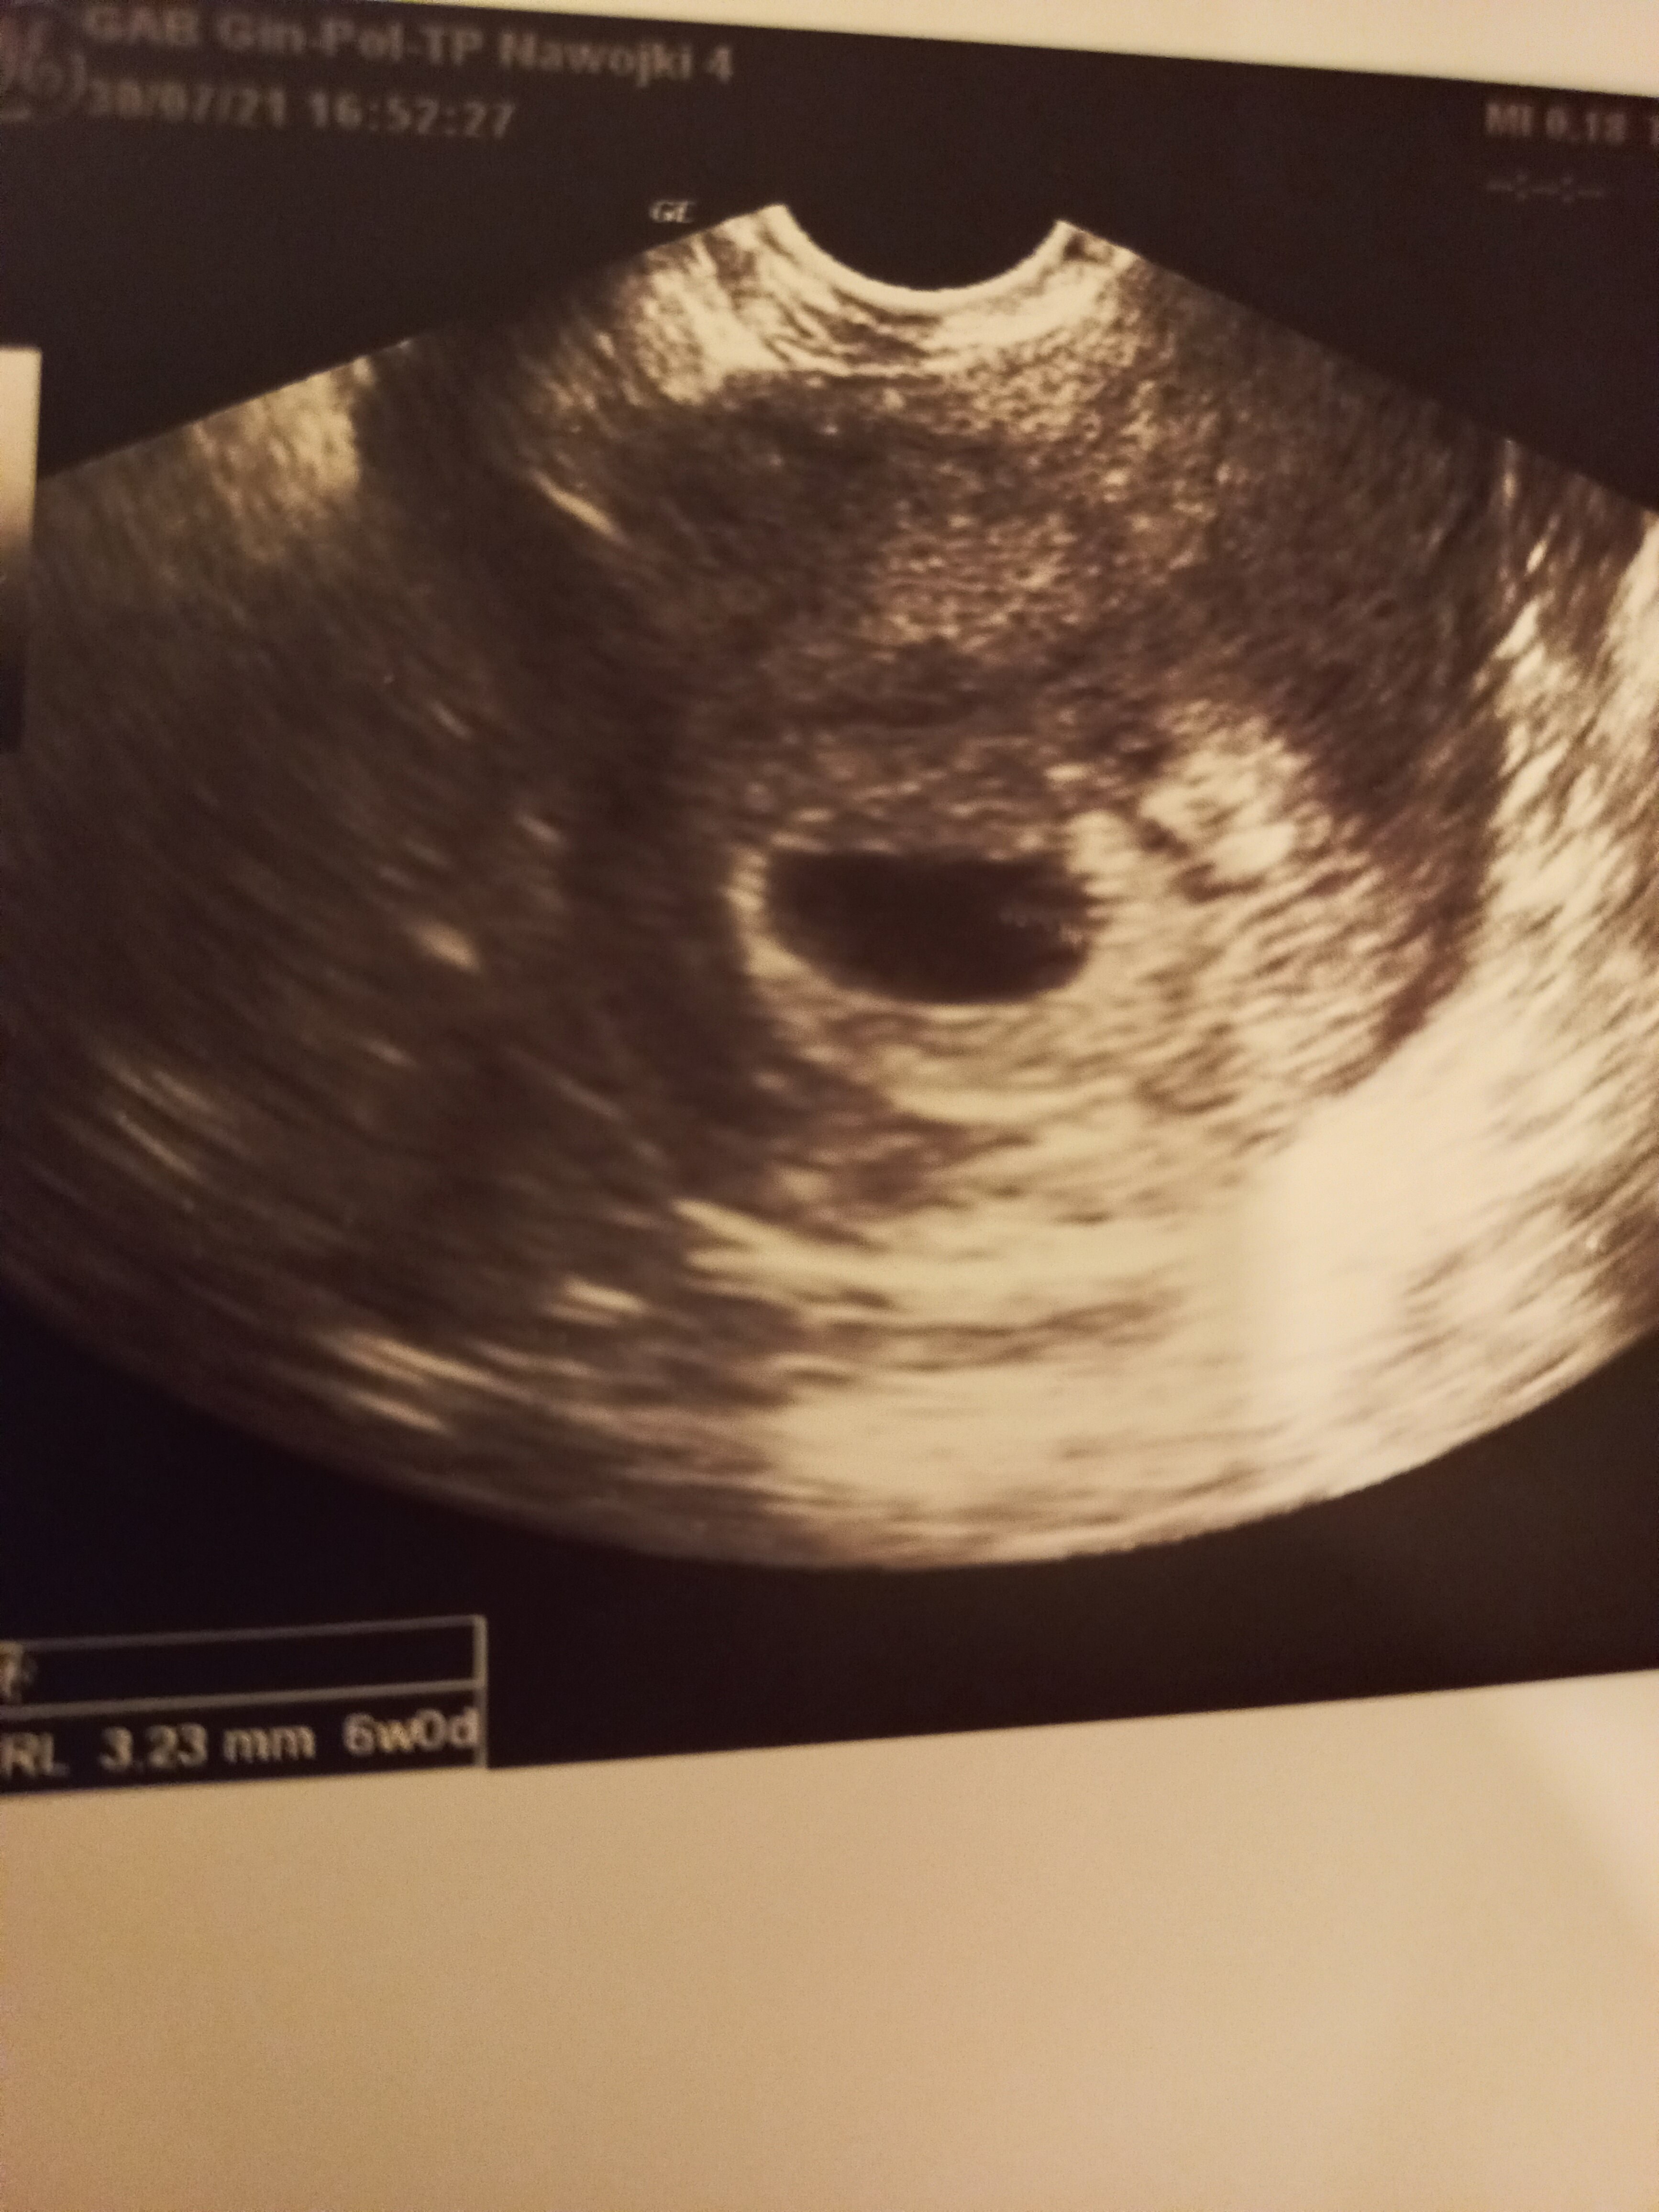

Dziewczyny jestem w 6 tyg 2 dniu ciąży . Niestety dziś będąc u lekarza usłyszałam , ze tętno jest za niskie 122 uderzenia i ze pęcherzyk zoltkowy jest spłaszczony i nie rokuje to dobrze. Mam się nie nastawiać na ta ciąże. Prawdopodobnie dojdzie do Poronienia. Czy ktoś był w takiej sytuacji ? Jak to się skończyło . Dodam ze pęcherzyk ciążowy jest dość duży jak na wiek mojej ciąży bo 20 mm pęcherz zoltkowy 3 a zarodek 3,1 . Proszę o pomoc bo tydzień czasu mam czekać do następnego usg a poprostu oszaleje.

Zoltkowy właśnie 😥

To usg jest od 2 lekarza na lepszym sprzęcie, na gorszym sprzęcie wyglądało jeszcze gorzej… cały pęcherz ciążowy nieregularny , ogólnie 2 lekarz staral się pocieszać, ze nie wszystko przesądzone , ale potwierdził ze pęcherzyk jest nieco spłaszczony

Zoltkowy jest spłaszczony , tak stwierdzili obydwaj lekarze. Jeżeli chodzi o tętno dziecko w 6 tyg a tętno 122. Drugi Psn doktor stwierdził , ze dopiero się rozkręca skoro tydzień temu nie było zarodka ma prawo takie być to tętno . Pani doktor stwierdziła ze powinno być do 160 uderzeń. W internecie wszędzie pisze ze od 100 do 140. Wszędzie inne informacje , zwariować idzie. Zgadzają się co pecherzyka zoltkowego, choć 2 pan doktor stwierdził , ze za wcześnie aby wyrokować . Myslalam , ze może ktoś już był w takiej sytuacji i może cokolwiek podpowiedzieć